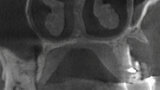

3D technologie v diagnostice a léčbě endodontických onemocnění